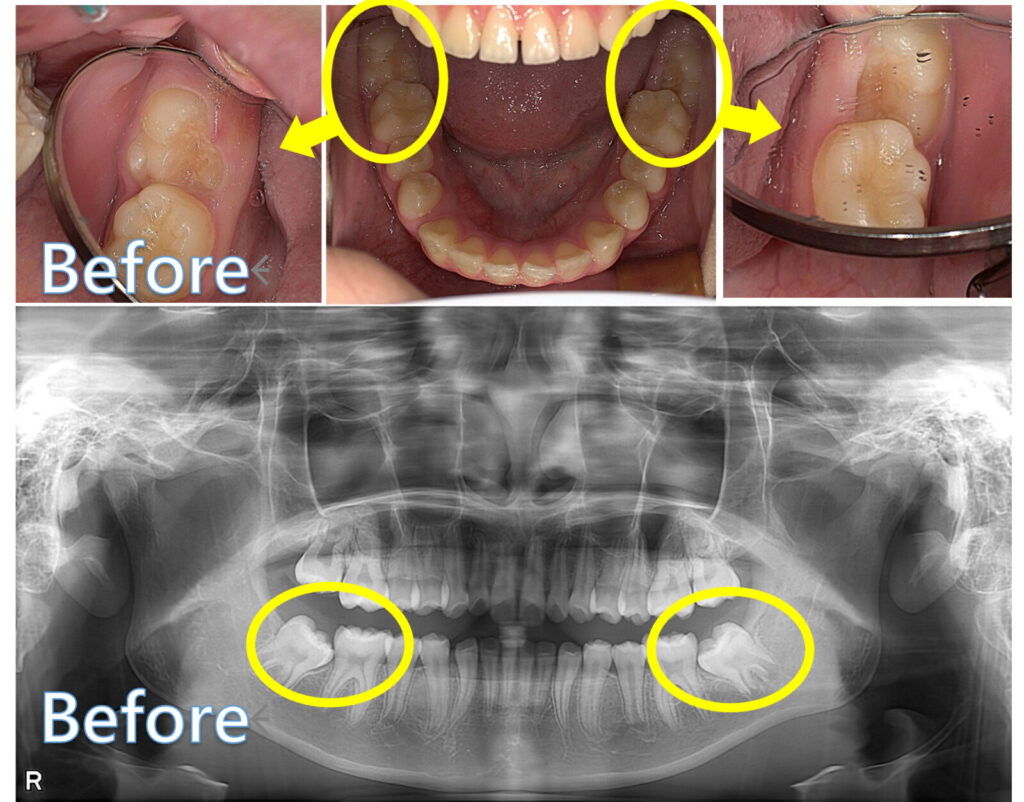

12歳臼歯(第二大臼歯)が斜めに生えてきたケース

ここからは、当院で実際に治療した症例をご紹介します。

この患者さんは、ほかの歯並びやかみ合わせには大きな問題がなかった一方で、12歳臼歯(第二大臼歯)だけが手前の歯にひっかかり、自力ではうまく生えてこられない状態でした。

術前の写真では、12歳臼歯が斜めの方向に傾いたまま生えてきていることがわかります。

このままでは自然な改善が難しいため、その歯だけを対象に矯正治療を行いました。